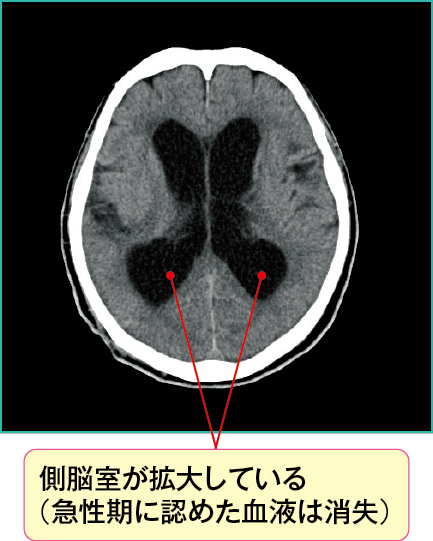

図3において側脳室が通常より拡大しており、正常圧水頭症を起こしています。

くも膜下出血慢性期に生じる水頭症は脳室の拡大を認めますが、急性水頭症のときに描写されていた血液は頭蓋内からなくなり、画像上では描写されません。

本症例は前交通動脈の動脈瘤破裂によるくも膜下出血(Hunt&Hess分類GradeⅤ)の、発症1年後の状態です。

くも膜下出血の慢性期で生じる正常圧水頭症は、急性水頭症の「交通性水頭症」の病態が緩徐に進行し、慢性的な髄液の循環障害が起こることで引き起こされます。

くも膜下出血慢性期の正常圧水頭症は交通性水頭症に分類され、通常、頭蓋内圧が亢進しないのが特徴です。そのため、くも膜下出血急性期の合併症の急性水頭症とは違い頭蓋内圧亢進症状はみられません。

図3の症例ではくも膜下出血により意識障害が残り、その後正常圧水頭症により、歩行障害と尿失禁が出現していました。